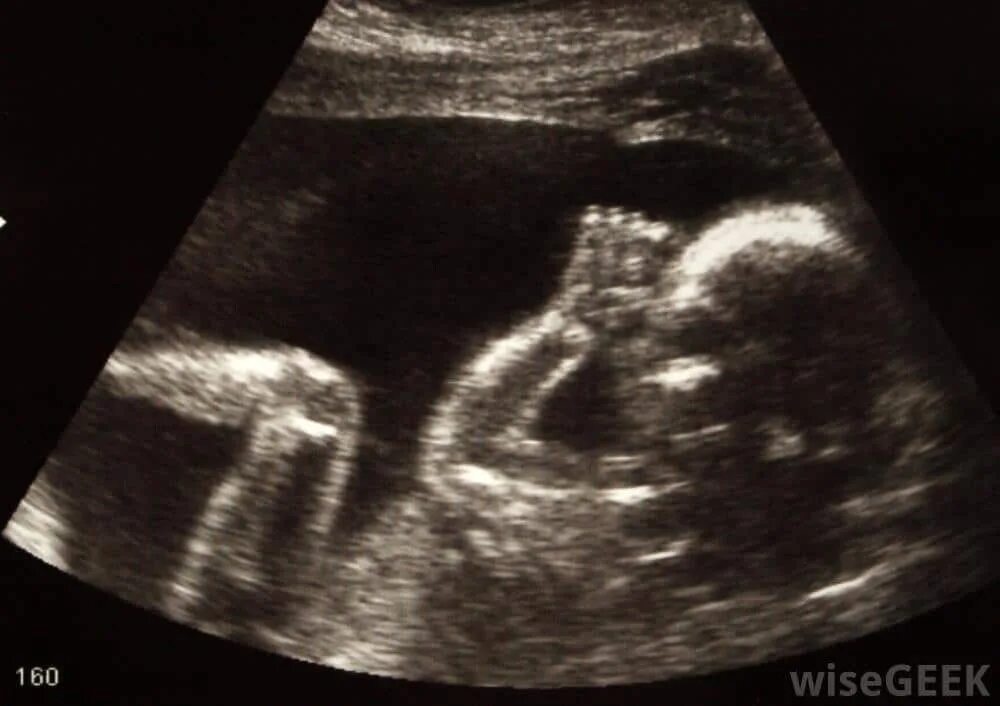

Скрининг 30 недель